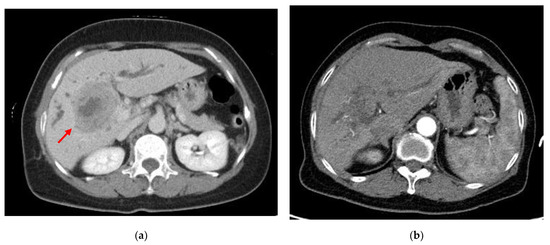

2. Case Presentation